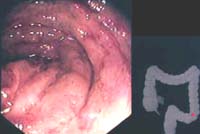

Figura 2. CI aguda leve: edema, petequias y erosión superficial.

Endoscópicamente, se encontraron áreas de equimosis, eritema, mucosa violácea en los 15 pacientes, y úlceras y membranas fibrinoides en el 67% de ellos (Figuras 1, 2, 3, 4 y 5).